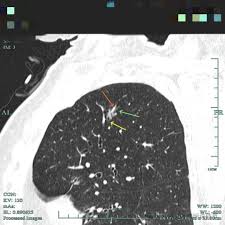

wl大心脏 请问心脏CT如何做增强处理?目前考虑的是尝试各种WWwl大心脏 WL,还有其他好方法吗?wl大心脏 wl大心脏 病例分享:多发结节又是多原发早期肺癌!浸润性也楔切是否真的合适?wl大心脏 當心理學家研發藥物——臺大賴文崧談思覺失調與多重系統退化症wl大心脏 劇烈肚子痛竟然是主動脈剝離wl大心脏 30歲男子脾臟腫大近2倍險破裂腹腔鏡微創手術開刀切除wl大心脏 wl大心脏 wl大心脏 wl大心脏 wl大心脏 wl大心脏 wl大心脏 wl大心脏 wl大心脏 wl大心脏 wl大心脏